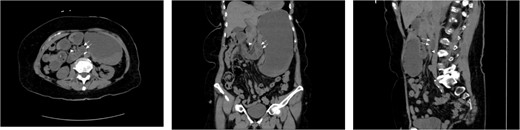

A 45-year-old morbidly obese male with a history significant for morbid obesity and atrial fibrillation presented with 1 day of abdominal distension, oral intake intolerance, nausea, and vomiting. The patient had no history of abdominal surgery. Physical exam revealed a soft, distended abdomen without peritoneal signs. Laboratory evaluation revealed normal blood cell counts and electrolytes. A CT-scan of the abdomen and pelvis with IV and PO contrast was performed which demonstrated proximal small bowel dilation and a significant amount of small bowel posterior to the SMA. A mesenteric swirl was also observed on CT imaging. The CT scan images are presented below (Fig. 4). Based on the concern for closed-loop obstruction and probable paraduodenal hernia, the patient was taken for diagnostic laparoscopy. During the procedure the patient was noted to have marked small bowel dilation, and most of the small bowel was found incarcerated behind the ascending mesocolon. The laparoscopic approach in this patient was significantly hindered by the excessive intraperitoneal fat present from his morbidly obese state. The procedure was converted to an upper midline laparotomy which facilitated complete reduction of the hernia and evaluation of the incarcerated bowel. Post-reduction, the bowel was deemed well perfused and viable. The internal hernia defect was confirmed as Waldeyer’s fossa based upon its position between the SMA and the ligament of Treitz. The hernia sac was opened laterally by mobilizing the cecum and ascending colon, taking down the white line of Toldt and medializing the ascending colon and cecum. Appendectomy was performed. The operation was completed without complication and the patient recovered well.

CT images for Case 2, axial, coronal, and sagittal, respectively. Note the mesenteric swirl (arrows in axial and coronal images) around the SMA (single arrowhead in axial and coronal images). This represents the posterior torsion of the small bowel mesentery as it courses into Waldeyer’s fossa toward the right retroperitoneum. The resulting dilated small bowel can be seen in the right upper quadrant. Also note the anterior course of the proximal transverse colon (three arrowheads in the sagittal cross-section) as it has been pushed toward the anterior abdomen due to the significant mass of dilated small bowel which is now posterior to its mesentery.